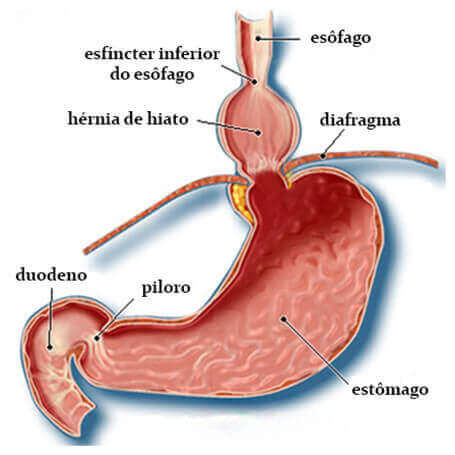

O tórax e o mediastino são separados do abdome por uma estrutura fibromuscular chamada de diafragma. O hiato diafragmático é o orifício ou abertura do diafragma por onde passa o esôfago. A transição esofagogástrica normalmente se situa imediatamente abaixo do diafragma e, quando esta está posicionada acima dele, estamos diante da hérnia de hiato:

Importante: A existência da hérnia de hiato favorece o aparecimento do refluxo, mas não é imprescindível a sua presença para termos a doença do refluxo gastroesofágico.